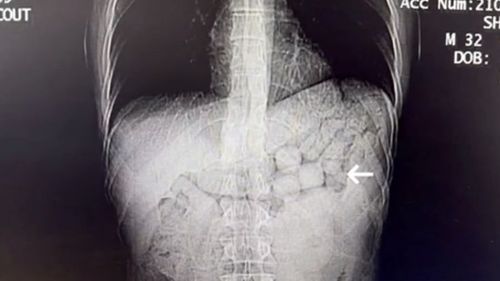

Diyarbakır'da midelerinde 91 kapsül halinde toplam 807,15 gram metamfetamin tespit edilen iki İranlı şüpheli, tutuklandı.

Diyarbakır'da midelerinde 807,15 gram uyuşturucu taşıyan iki İranlı tutuklandıDiyarbakır Emniyet Müdürlüğü Narkotik Suçlarla Mücadele Şube Müdürlüğü ekipleri, uluslararası uyuşturucu madde ticaretine yönelik yürüttükleri operasyonda iki yabancı uyruklu şüpheliyi yakaladı.Operasyon ve tespitİran'dan ülkeye uyuşturucu getireceği değerlendirilen şüpheliler, Diyarbakır Şehirlerarası Otobüs Terminalinde…